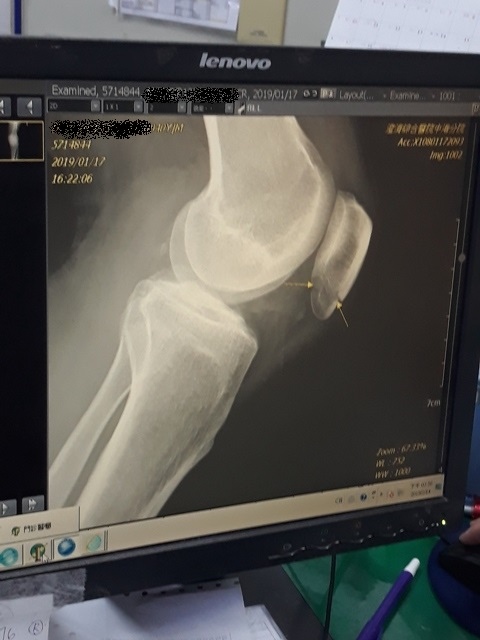

今日所拍的X光照↓

這三次回診的X光片,相較前兩次,今天已經癒合許多了↓

或許今天是228放假日,來醫院看病的人蠻多的,我們等了一段時間才被叫到。進到診間後,黃醫師調出X光資料,發現橈骨已癒合很多了,讓我感到很吃驚,兩個星期前還是很明顯的骨裂,現在已經看不太到了(小純說,一定是峰王膠原飲發揮了功效,這兩週內,膠原蛋白喝了八罐了)。黃醫師說,我的手腕護具可以拿掉了,我拿起護具後,黃醫師拉了我的手腕做一些轉動的動作,還是有些痛,黃醫師叫我要多做熱敷,手可以開始做復健了,也可以讓手開始做一些事情,但避免提重物,兩個星期後再回診看角度。

進入門診前,我自認為手比腳恢復還快,因為比起一開始,手指比較能出力了,手腕可轉動的範圍也變大了。腳因一直用副木石膏固定住,不能動,所以也不知恢復多少。進入門診後,黃醫師說斷裂的骨頭都沒移位。手沒什麼進展(骨頭不會長那麼快),腳的部份下回再來復診時,可能會恢復的較快了。